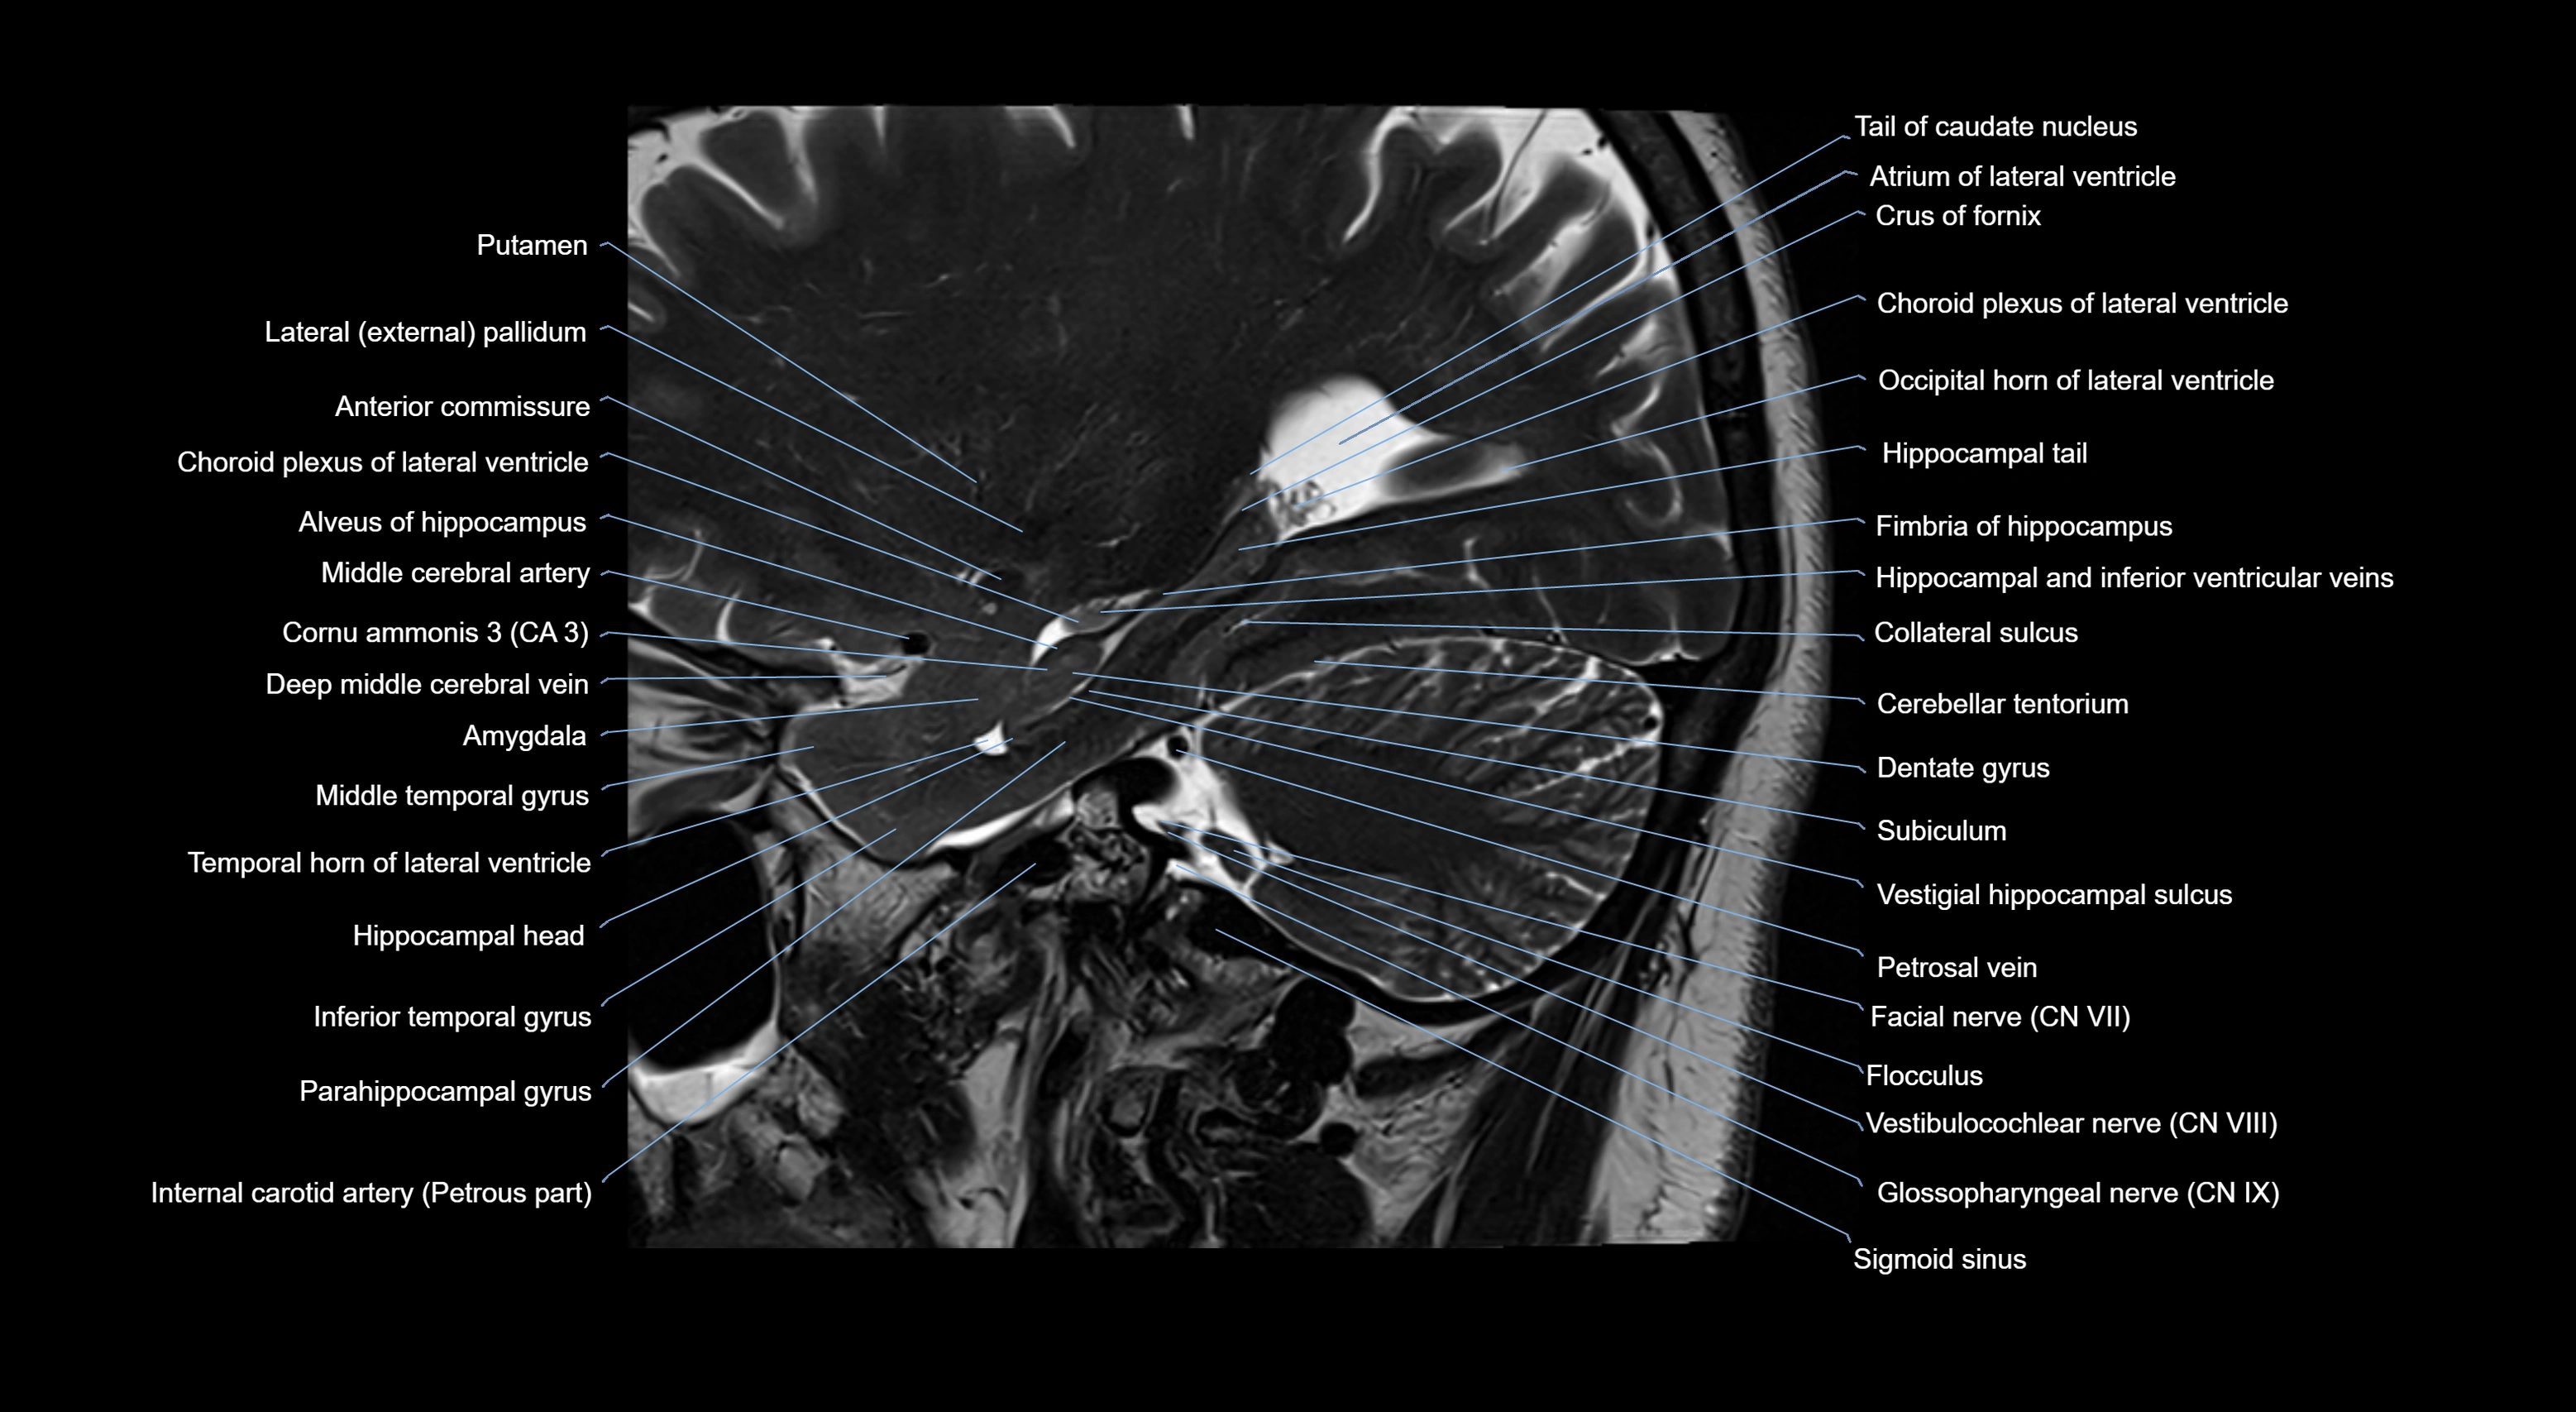

MRI images